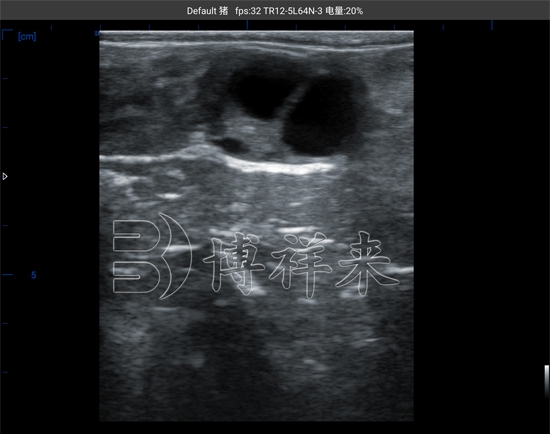

在母牛的发情周期中,卵巢内会经历一系列卵泡发育和退化的过程。一般情况下,一个完整的发情周期大约为21天,在周期内会出现多个卵泡波,但最终只有优势卵泡能够成熟并排卵。通过使用牛用B超机对母牛卵巢进行扫描,技术人员可以在屏幕上清晰看到卵泡的形态和大小变化。超声图像中,卵泡通常呈现为黑色圆形或椭圆形的无回声区域,边界清晰,通过测量其直径即可判断卵泡的发育阶段。通常情况下,当优势卵泡直径逐渐增大并接近成熟阶段时,就意味着排卵时间即将到来。

BXL-V50 测牛卵巢卵泡大小超声图